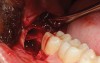

A presurgical rinse of 0.2% chlorhexidine (CHX) solution was performed, followed by administration of local anesthetic using 4% articaine with epinephrine solution. A crestal incision with a vertical releasing incision at the mesial aspect of the surgical area was made, and a full-thickness mucoperiosteal flap was elevated (Figure 1). A buccal and, if required, distal osteotomy was performed using a round carbide bur on a straight handpiece. When necessary the tooth was dissected to allow it to be elevated and extracted (Figure 2). When performing the third molar extraction care was taken to not damage the adjacent second molar tooth nor its supporting alveolar bone. The extraction socket was thoroughly debrided with hand instruments and rinsed with a 0.2% CHX solution to decrease bacteria in the socket (Figure 3).35

The extracted tooth fragments were cleaned to remove caries if present as well as periodontal ligament (PDL) remnants (Figure 4). The tooth was ground into particles using the dentin grinder machine. The particles were then saturated for 10 minutes in a dentin cleanser solution (sodium hydroxide solution mixed in 20% ethanol); this was followed by a phosphate buffered saline wash, resulting in a bacteria-free, autogenous graft material ready for implantation (Figure 5).

Fig 3. Extraction socket after removal of the impacted mandibular third molar.

Figure 3